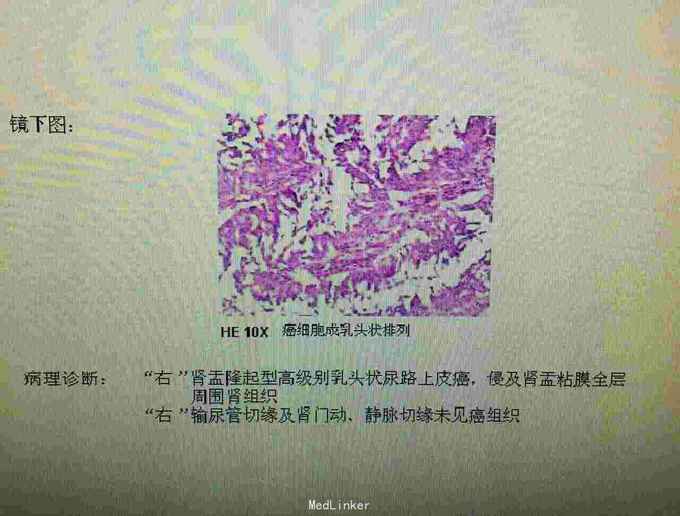

病理诊断为:右肾盂隆起型高级别乳头状尿路上皮癌,未侵及被膜。